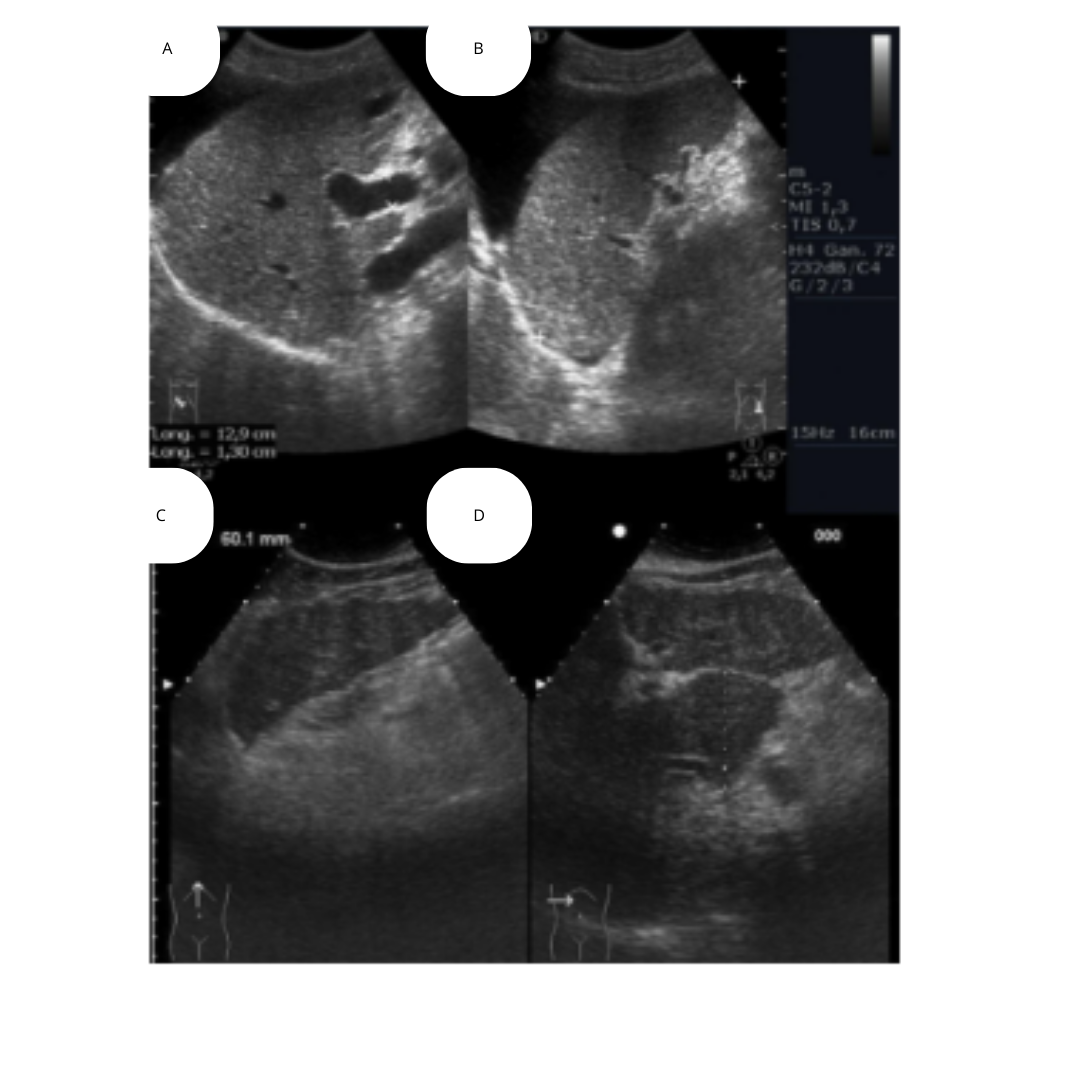

Figura 2: Las imágenes muestran irregularidad de superficie, ascitis y los patrones nodulares.

Figura 3: A.- Dilatación de la porta y ascitis. B.- Esplenomegalia. C.- Lóbulo hepático izquierdo con bordes irregulares. D.- hipertrofia del lóbulo